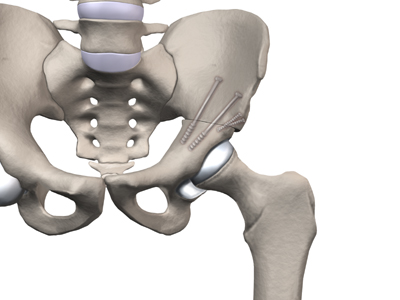

Surgical treatment for containment usually consists of procedures that realign the femur (thighbone), the acetabulum (hip socket), or both.

Realignment of the femur is called a femoral osteotomy. This procedure changes the angle of the femoral neck so that the femoral head points more towards the socket. To perform this procedure, an incision is made in the side of the thigh. The bone of the femur is cut and realigned in a new position. A large metal plate and screws are then inserted to hold the bones in the new position until the bone has healed. The plate and screws may need to be removed once the bone has healed.

In severe cases, both femoral osteotomy and pelvic osteotomy may be combined to obtain even more containment.